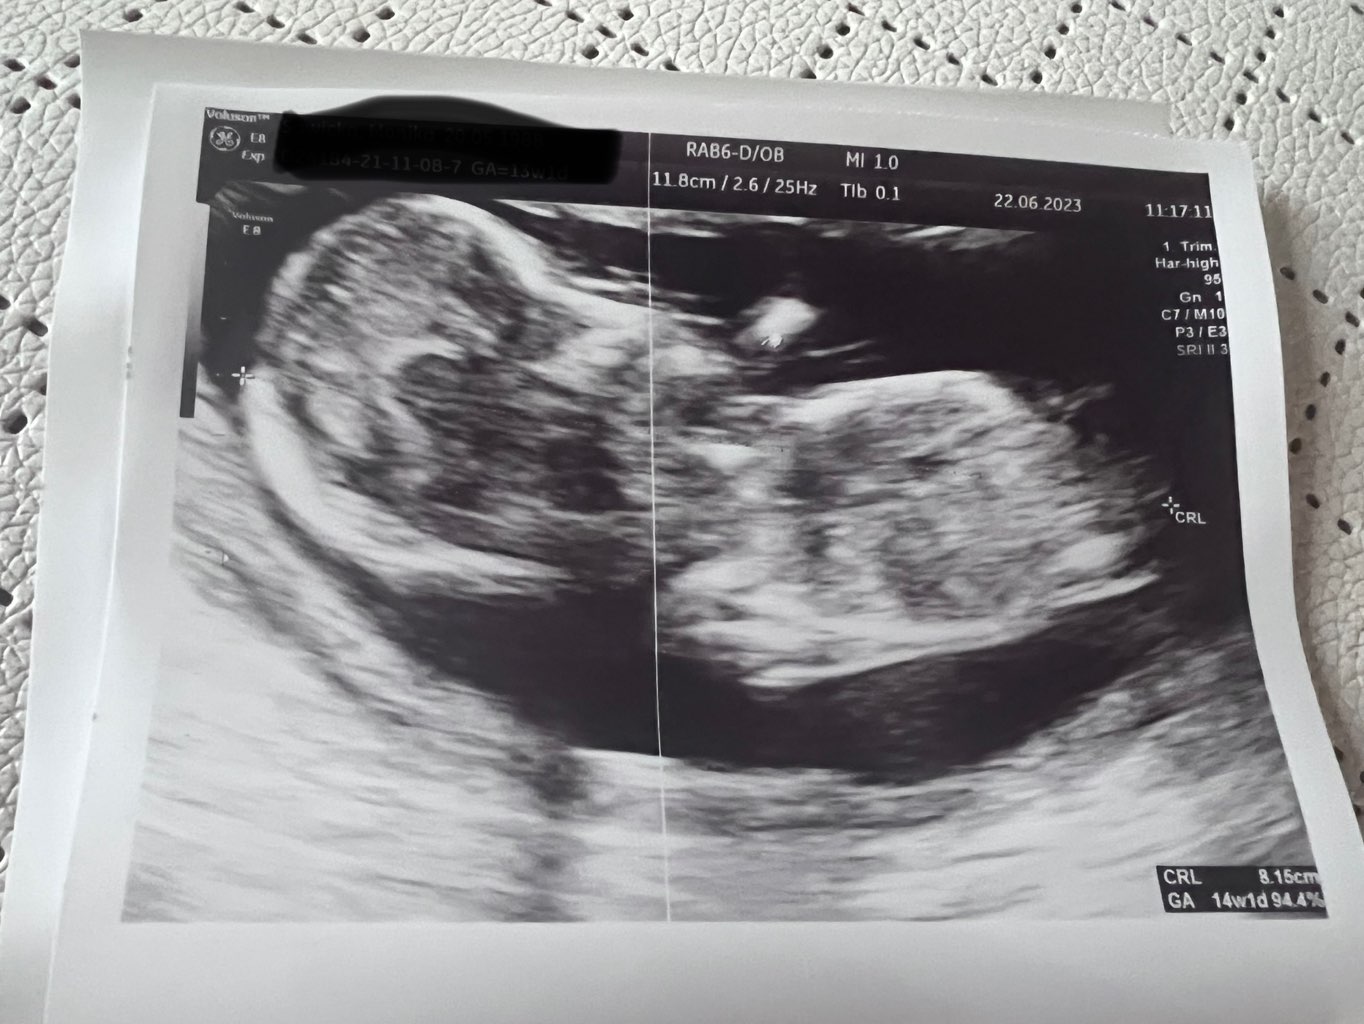

Na obrazie widać ukrwienia przy przepływach na łożysku, ale on nie jest w stanie mi powiedzieć czy to jest cecha wrastającego łożyska, bo nie jest od tego specjalistą. Mam mu dać znać, jak będę po szpitalu co powiedzą (on będzie na urlopie, ale odczytuje maile). Potem przeszliśmy do kości, trochę się musiał nagimnastykować, żeby dobrze ustawić widoczność (pukał mnie po brzuchu i dziecko skakało

) i udało się zrobić zdjęcia z kursorem gdzie widzi i jest kość nosowa (załączam

). Czekamy na wyniki Pappy, powiedział, że w moim wieku i z tym, że w opisie USG prenatalnym jest ta kość brak/hypoplastyczna to pewnie ryzyko będzie podwyższone. Jak już te będą to wtedy będziemy ewentualnie myśleć o amniopunkcji.